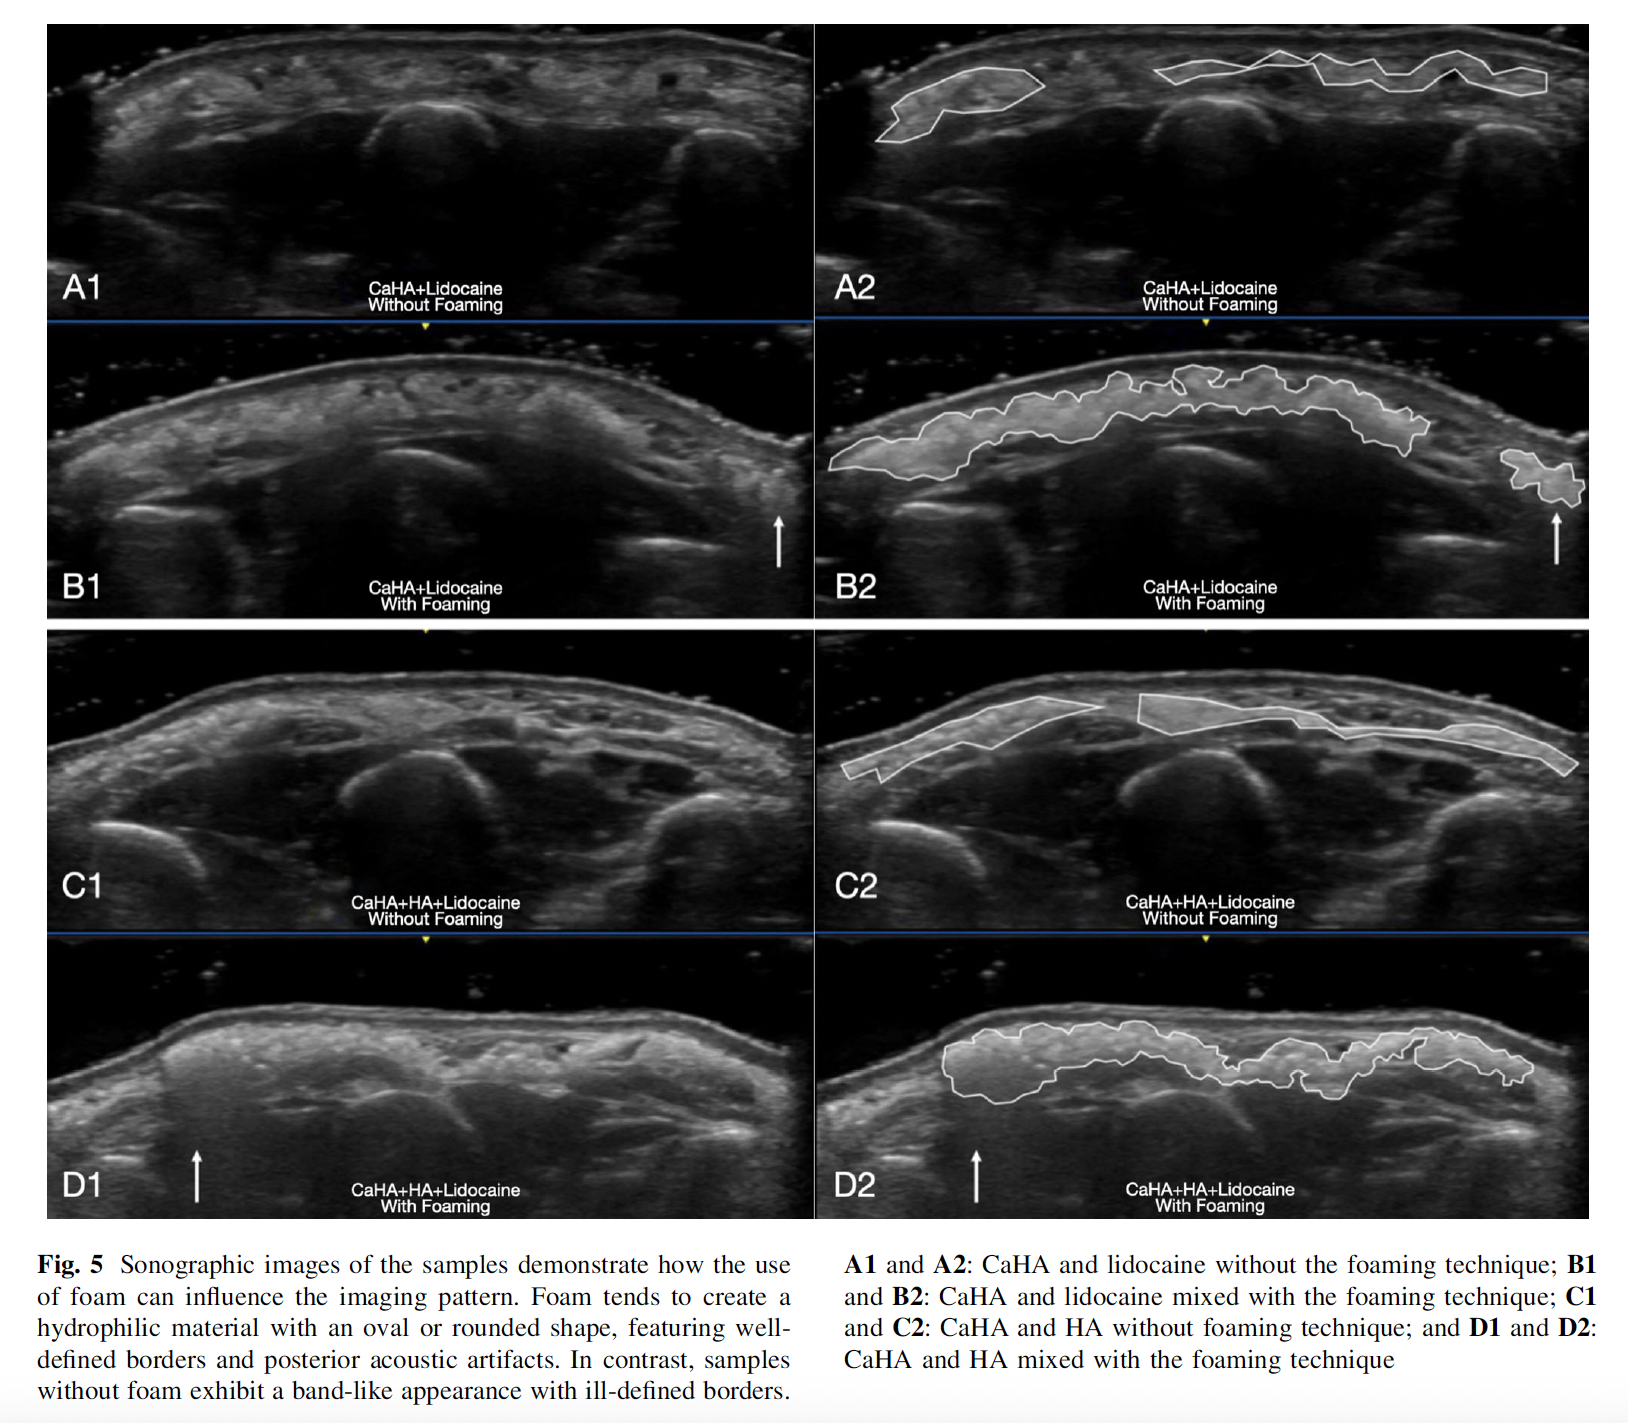

Skany SEM pokazały gładsze, bardziej jednorodne „pomosty” między cząstkami i zachowanie rozmiaru sfer CaHA, a badanie jednorodności wykazało niższe odchylenia między próbkami po spienieniu niż przy standardowym mieszaniu – co praktycznie przekłada się na mniejszą liczbę koniecznych ruchów mieszających dla uzyskania homogeniczności. Sonografia (18–24 MHz) ujawniła owalne depozyty o wyraźnych granicach i z charakterystycznymi pęcherzykami związanymi z gazem w pianie. Bez foamingu obraz miał częściej postać mniej wyraźnego „pasma”. W badaniu nie stwierdzono żadnych poważnych działań niepożądanych – jedynym incydentem był łagodny obrzęk, który ustąpił w ciągu dwóch tygodni. W praktyce foaming technique sprawia, że preparat łatwiej rozprowadza się w formie równych nitek, szczególnie w głębszych warstwach tkanek, co zwiększa zasięg biostymulacji i daje większą swobodę w wyborze obszaru podania.